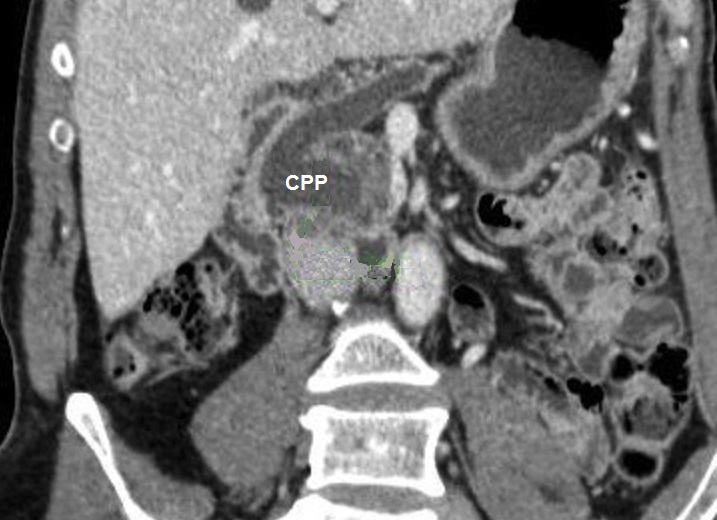

Sus les coupes IRM pondere

sur T2 Image radiolofique des TIPMP de type canaux

secondaire sont des kystes unique ou multiple

arondie ou ovalaire polylobulaire de fortement

hyperintense et comunication souvent avec canal

principale CPP ( fleche rouge ) . Image radiologique

IRM ponderation sur T2 , en coupe axiale |